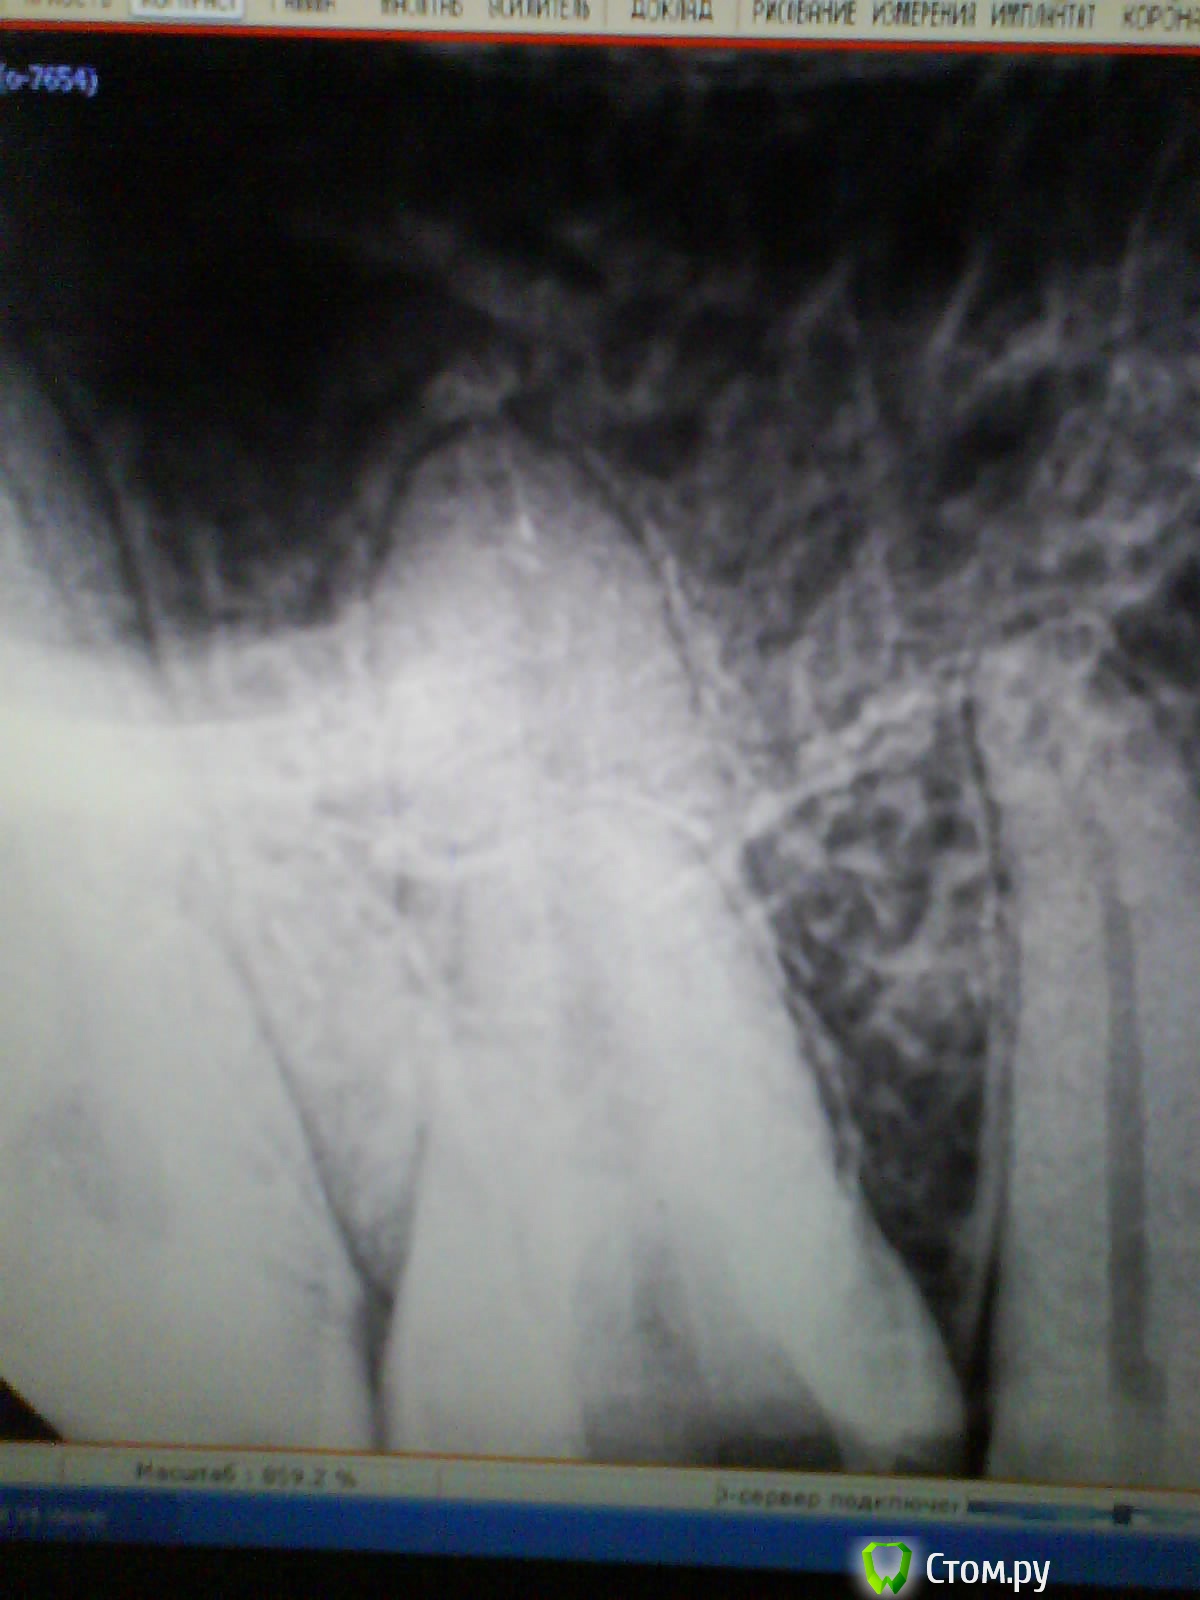

Scathach Опубликовано 20 декабря, 2013 Автор Поделиться Опубликовано 20 декабря, 2013 Дорогие докторы, выкладываю снимки. Прошу прощения за качество, пришлось шпионски снимать на телефон) Другой стоматолог сказала, что ничего криминального не во рту, ни на снимке не наблюдает.Высказала варианты: 1) корень зуба заходит в гайморову пазуху2) есть-таки маааленький хронический периодонтит3) разыгрался травматический периодонтит из-за кривой пломбы За три дня в открытом состоянии вроде стало чуточку полегче, но в целом картина прежняя - пока зубом я не жую, он остро не болит, но много раз в день возникают странные ощущения в десне, её как бы распирает немного изнутри и зуб кажется "больше" других, потом это пропадает. При постукивании зуб не болит вообще, на горячее не реагирует. Боль только когда сильно смыкаются зубы при жевании. И зуб, и десна по ощущениям (языком) намного теплее, чем "соседи". Десна при нажатии болит точно над зубом (высоко, там где уже чувствуется кость и начинается ткань щеки). Есть что-то типа маленькой болезненной штучки в этом месте, если пощупать пальцем, но никакого открытого свища и пр. нет. Ссылка на комментарий

red_butler Опубликовано 21 декабря, 2013 Поделиться Опубликовано 21 декабря, 2013 Ничего страшного не увидел, как можно скорее долечивайте зуб. Зуб оставлять открытым нельзя, происходит массивное обсеменение корневых каналов микроорганизмами из слюны. Найдите стоматолога эндодонтиста владеющего современными протоколами лечения корневых каналов Ссылка на комментарий